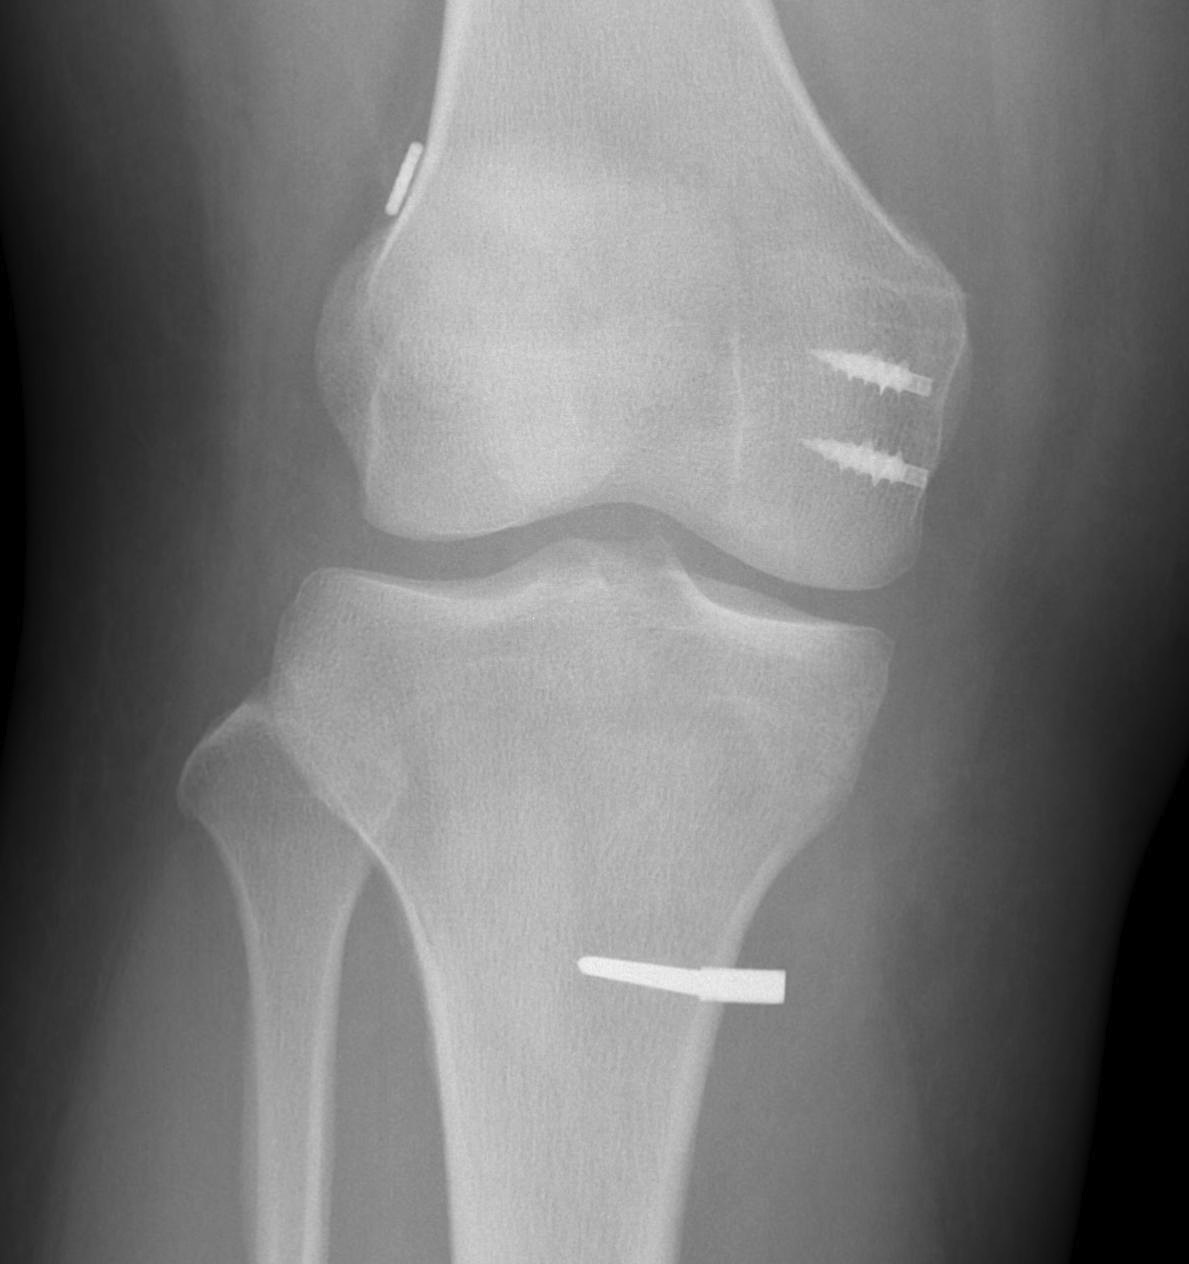

X-ray

Usually normal in acute injury

Bony avulsions (rare)

Bony avulsion of MCL on femoral side

Pellegrini-Stieda Lesion

- calcification at insertion of femoral MCL

- indicative of chronic injury

Bony MCL Avulsion

Elevate VMO and repair with staples or screw